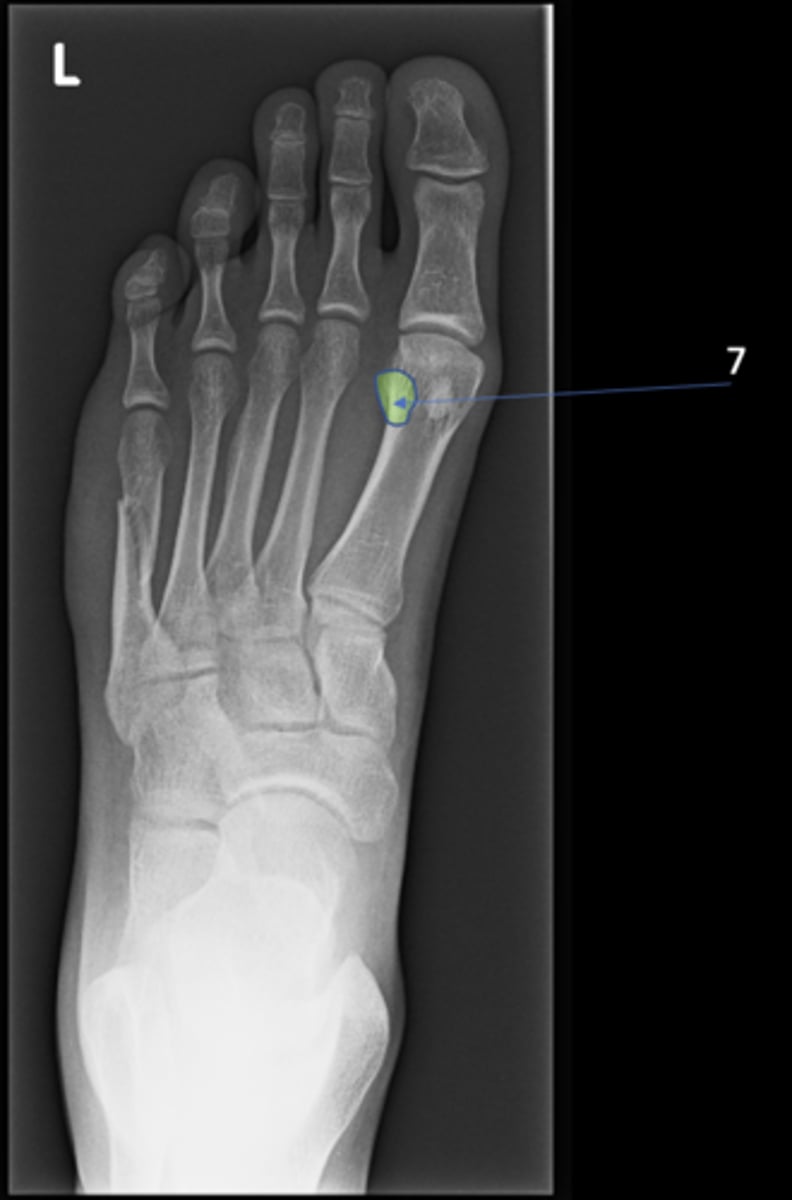

New cards

Left inferior pubic ramus

ID 15

<p>ID 15</p>

15

S1 tubercle

ID 16

<p>ID 16</p>

16